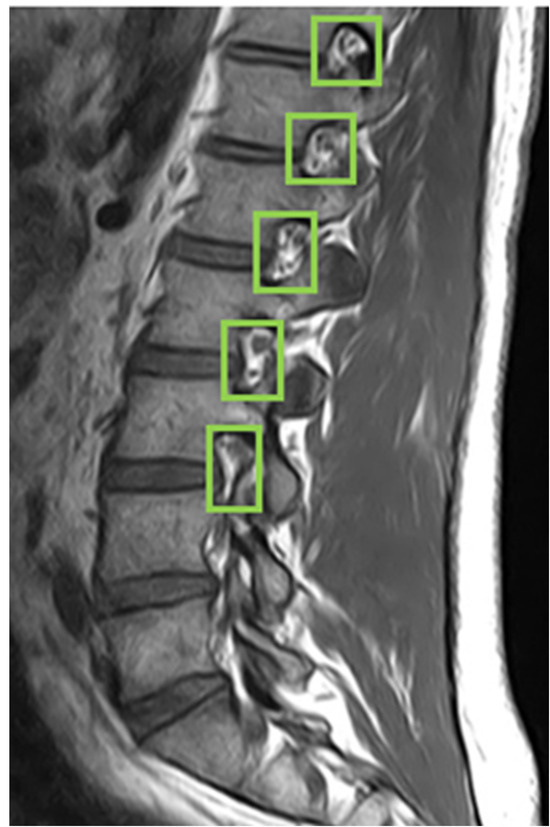

4.3. Intervertebral Foramen Identification